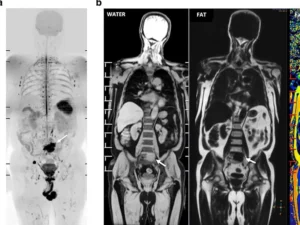

Tüm vücut MR, manyetik rezonans görüntüleme teknolojisi kullanılarak vücudun tamamının ayrıntılı bir şekilde taranmasıdır. Radyasyon içermeyen bu yöntem, manyetik alan ve radyo dalgaları yardımıyla organların ve dokuların yapısını detaylı bir şekilde gösterir. Doktorlar, bu görüntüleri kullanarak hastalıkları teşhis eder ve tedavi planlarını oluşturur.

Tüm Vücut Emar için kullanılan MR Cihazlarımız en yeni teknolojiye sahip 3 Tesla özelliğine sahiptir. Tüm Vücut Emar yüksek çözünürlüklü ve çok net görüntüler doğru teşhis için son derece önemlidir. Tüm Vücut emar için anestezili seçenekler de mevcuttur.